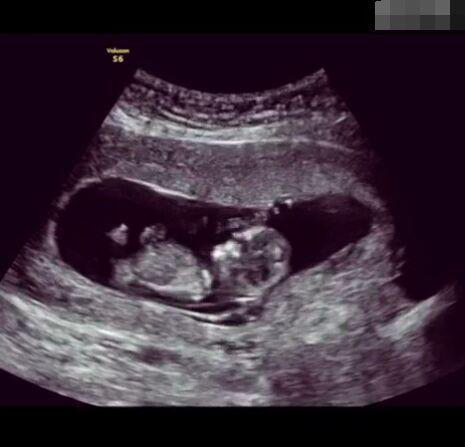

孕育生命是一件無比非凡的事!想像一下,我們都是從一個肉眼難見的小小受精卵發(fā)育而來,而這只需要一顆卵子與一顆精子的結合,就能實現(xiàn)一個生命的從無到有的過程,這是多么神奇的一件事情!

圖片2.png

懷孕后,寶寶的性別一直是全家人的重點關注對象。而男女性別的差異,在基因層面體現(xiàn)在第二十三對染色體上,如果是XY則是男孩,XX則是女孩,這都是由那枚與卵子結合的精子來決定。

圖片8.png

那些做了B超檢查確定胎兒男女,生下來后發(fā)現(xiàn)不對的,多半是因為在B超檢查時寶寶太調皮,以致影響了檢查準確性。就比如說,有的女寶寶在媽媽肚子里玩自己的臍帶,把臍帶夾到了兩腿中間,B超就有一定幾率拍出來好像是男寶寶的特征,導致被誤認為是男孩子。還有些男寶寶過分害羞,在做B超時雙腿緊緊并攏,醫(yī)生也很難判斷男女,只好大致猜測是女孩,就又造成了誤會。因此,B超亦不是萬能的。